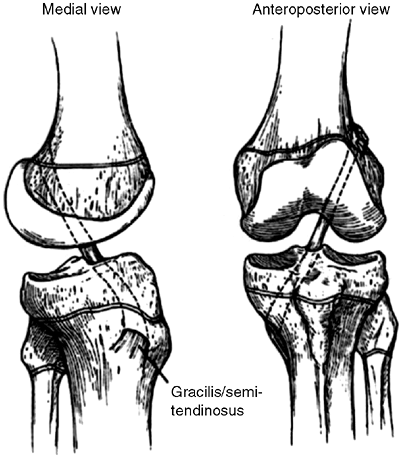

reconstructed using a free hamstring graft, usually the semitendinosus (33). The graft is anchored by suture anchors at the adductor tubercle and to the medial superior border of the patella.

a vastus medialis obliquus (VMO) advancement distally and laterally

with medial reefing will correct the medial deficiency (54,55,56). In a child 12 years or younger, the medial reefing may be augmented by the semitendinosus tenodesis described by Galeazzi (57,58).

This graft reproduces the vector of the patellotibial ligament. It is

employed when there is persistent instability after already performing

a lateral release and MPFL reconstruction or VMO advancement (Fig. 32.4).

Figure 32.4

The Galeazzi procedure transfers the semitendinosus to the inferior pole of the patella. From there, it courses through a drill hole placed obliquely through the patella, exiting the superior lateral aspect. The tendon is then sutured to the soft tissues. This provides a medial tether and effectively alters the net vector of the patellar tendon toward the medial side. Typically, the vastus medialis is advanced approximately one-third the width of the patella. |